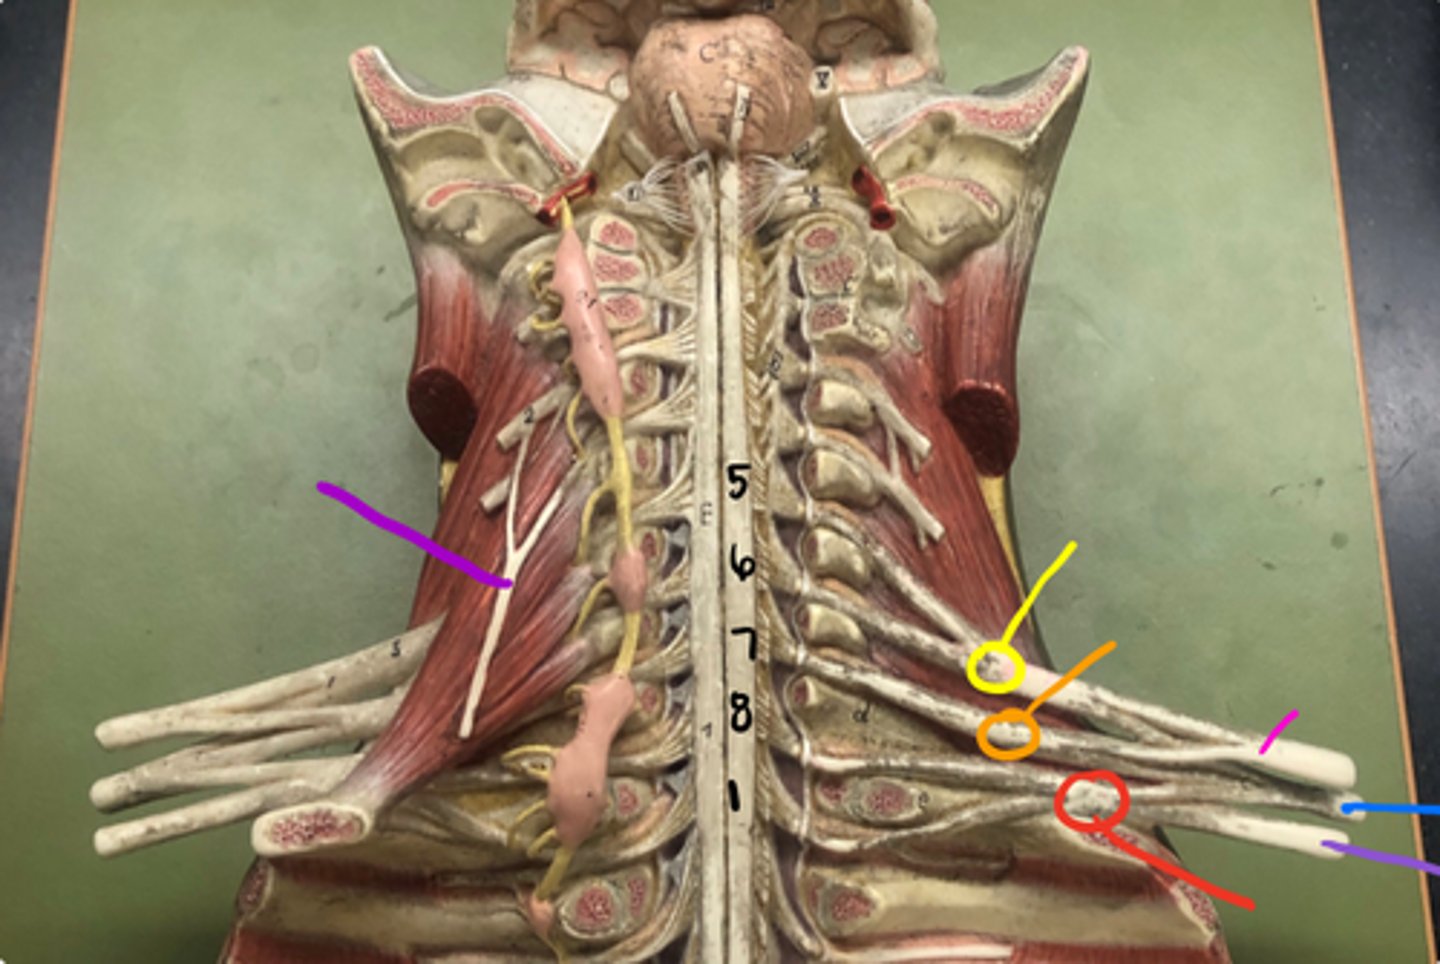

superior trunk

yellow

middle trunk

orange

inferior trunk

red

lateral cord

pink

medial cord

purple

posterior cord

blue

musculocutaneous nerve

median nerve

ulnar nerve

axillary nerve

dives deep near teres major

radial nerve

suprascapular nerve

Branches off the superior trunk

Seen on cadavers or picture

Subscapular nerve